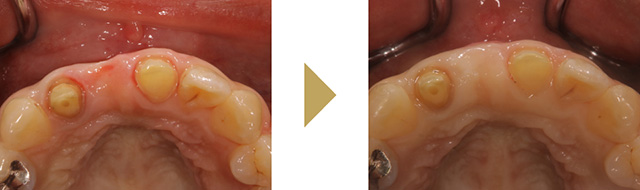

例えば、歯を抜いたところ等は歯茎が痩せやすく凹んでしまうことがあります。

凹みは汚れが溜まりやすい為、虫歯や歯周病の原因になってしまったり、ブラッツシング圧が強いと、歯茎が極端に痩せてしまい歯の根が露出し知覚過敏になることもあります。